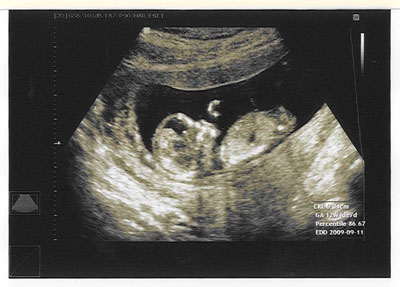

örömmel tudatom veletek, hogy Csöppkével minden a lehető legnagyobb rendben, hála Istennek!!!!!!!!

El sem tudom mondani, micsoda megkönnyebbülés, hogy jól van, rendben van....

BDP 18mm

AC 55mm

CRL 50 mm

nyaki redő 1,8 mm-norm :)

A számítottnak megfelelő terhességi kor, 11 hét 5 nap

magzatvíz mennyisége átlagos, lepény mellső falon tapad jó helyen.

Van miért hálát adni!

Szóval nagy kő esett le a szívemről :) Képet is kaptunk, Csöppke épp aludt, s úgy néz ki a drága, mint E.T. :))))) Szerintem nem tudom majd felrakni, mert a scann-nél nagyon sötét lesz, de majd Apa varázsol talán valamit :) Ati úgy bámulta a monitort a vizsgálat alatt, esküszöm , mintha tudta volna, hogy a tesót nézzük :) Egyébként jól bírta a gyűrődést nagyon, Dokibával lekezelt :lol: a kismamákat az ujja köré csavarta :lol: :lol: :lol: